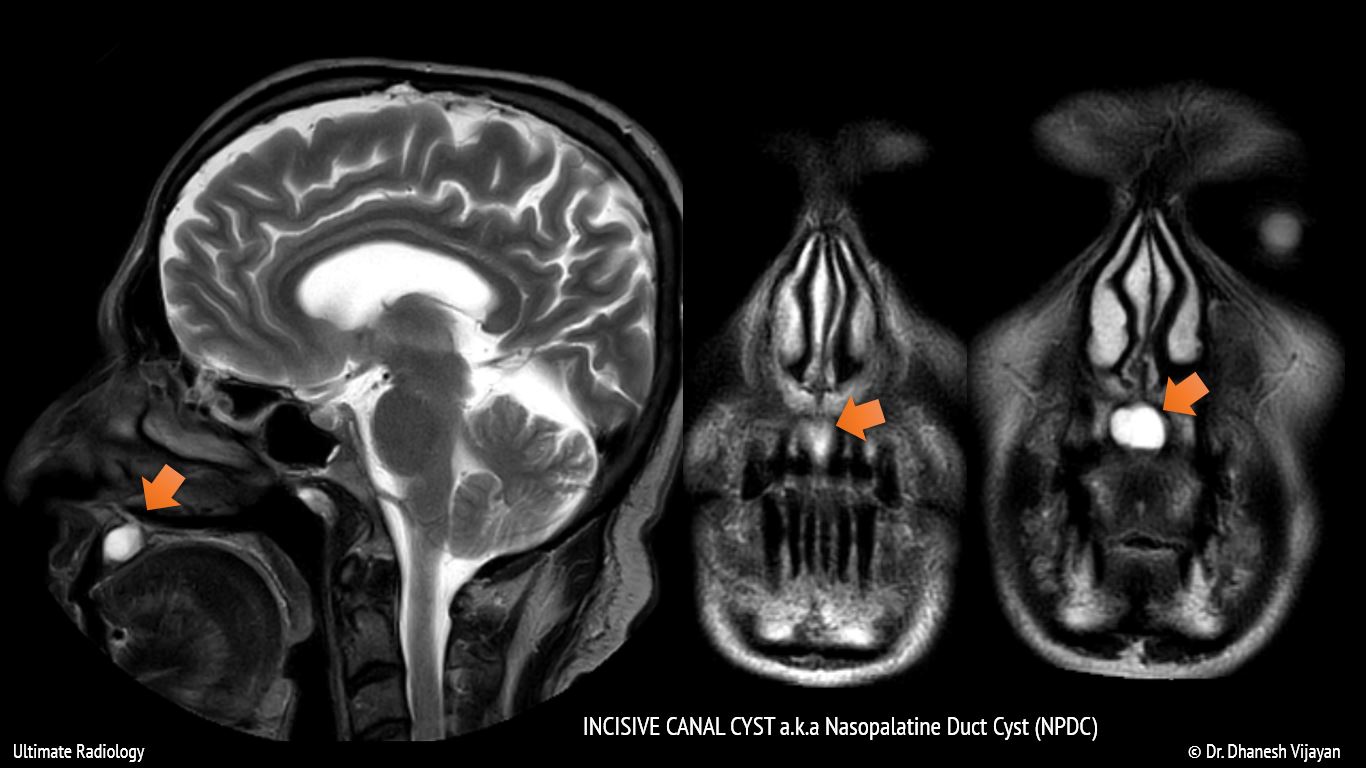

From www.vrogue.co

Ultimate Radiology Incisive Canal Cyst Nasopalatine D vrogue.co Incisive Canal Cyst Symptoms The incisive canal, also known as the nasopalatine canal, is an interosseous. It appears as either asymptomatic which is recognized on routine. Incisive canal cysts, also known as nasopalatine duct cysts (npdcs), are developmental, nonneoplastic cysts arising from degeneration. Nasopalatine duct cyst, also termed as incisive canal cyst, arises from embryogenic. T he nasopalatine duct cyst (npdc), also known as. Incisive Canal Cyst Symptoms.

From ultimate-radiology.blogspot.com

Ultimate Radiology Incisive Canal Cyst (Nasopalatine Duct Cyst) Incisive Canal Cyst Symptoms It appears as either asymptomatic which is recognized on routine. The incisive canal, also known as the nasopalatine canal, is an interosseous. T he nasopalatine duct cyst (npdc), also known as the incisive canal cyst, is the most common nonodontogenic cyst of the oral. They present as swelling of anterior hard palate, sometimes associated with pain and drainage. Nasopalatine duct. Incisive Canal Cyst Symptoms.

Ultimate Radiology Incisive Canal Cyst (Nasopalatine Duct Cyst) Incisive Canal Cyst Symptoms It may appear as extrabony incisive papilla cyst or intrabony lesion. They present as swelling of anterior hard palate, sometimes associated with pain and drainage. The incisive canal, also known as the nasopalatine canal, is an interosseous. Incisive canal cysts, also known as nasopalatine duct cysts (npdcs), are developmental, nonneoplastic cysts arising from degeneration. T he nasopalatine duct cyst (npdc),. Incisive Canal Cyst Symptoms.